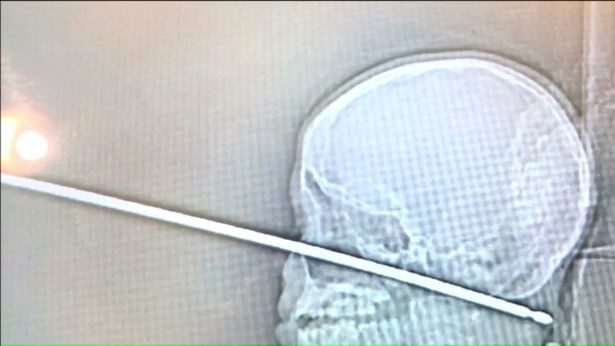

10-летнему Ксавьеру Каннингему из Миссури, США, крупно повезло — металлический стержень не повредил ни мозг, ни артерии, и врачи успешно извлекли предмет.

Ребёнок поднимался по лестнице, чтобы поиграть в домике на дереве, когда его внезапно атаковал рой ос, в результате чего Ксавьер кинулся бежать. Пытаясь спастись, мальчик упал на землю и угодил лицом прямо на торчащий 30-сантиметровый шампур, пишет The Sun.

Тот прошёл до самого затылка, но таким образом, что обошёл все важные внутренние части головы. Родители мальчика называют это не меньше чем чудом. Если бы он ненамного сместился, Ксавьера ждала бы верная смерть.

Он прошёл, не задев полушария и ствол головного мозга, черепные нервы — всё важное в голове

Ребёнка срочно доставили в больницу в Канзасе, где в ходе длительной операции врачам удалось успешно извлечь металлический стержень. Мальчик уже пришёл в себя и даже поиграл в приставку и пошутил с родителями. Медики надеются на его быстрое восстановление и вскоре планируют отпустить домой.